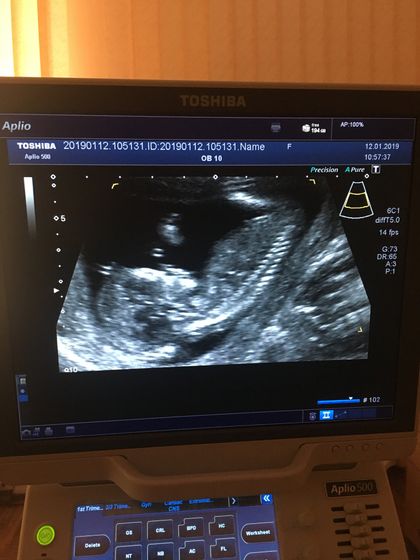

Сегодня ураааа!!! Был первый скрининг:) сделали узи, взяли кровь :) развивается немного быстрее :) обычно недели считала по средам недели, теперь буду по понедельникам:) получается завтра уже 14 неделек:)☺️ 7.9 см от копчика до темечка:)

Только вот в заключении узи написано « гипертонус по задней стенке»